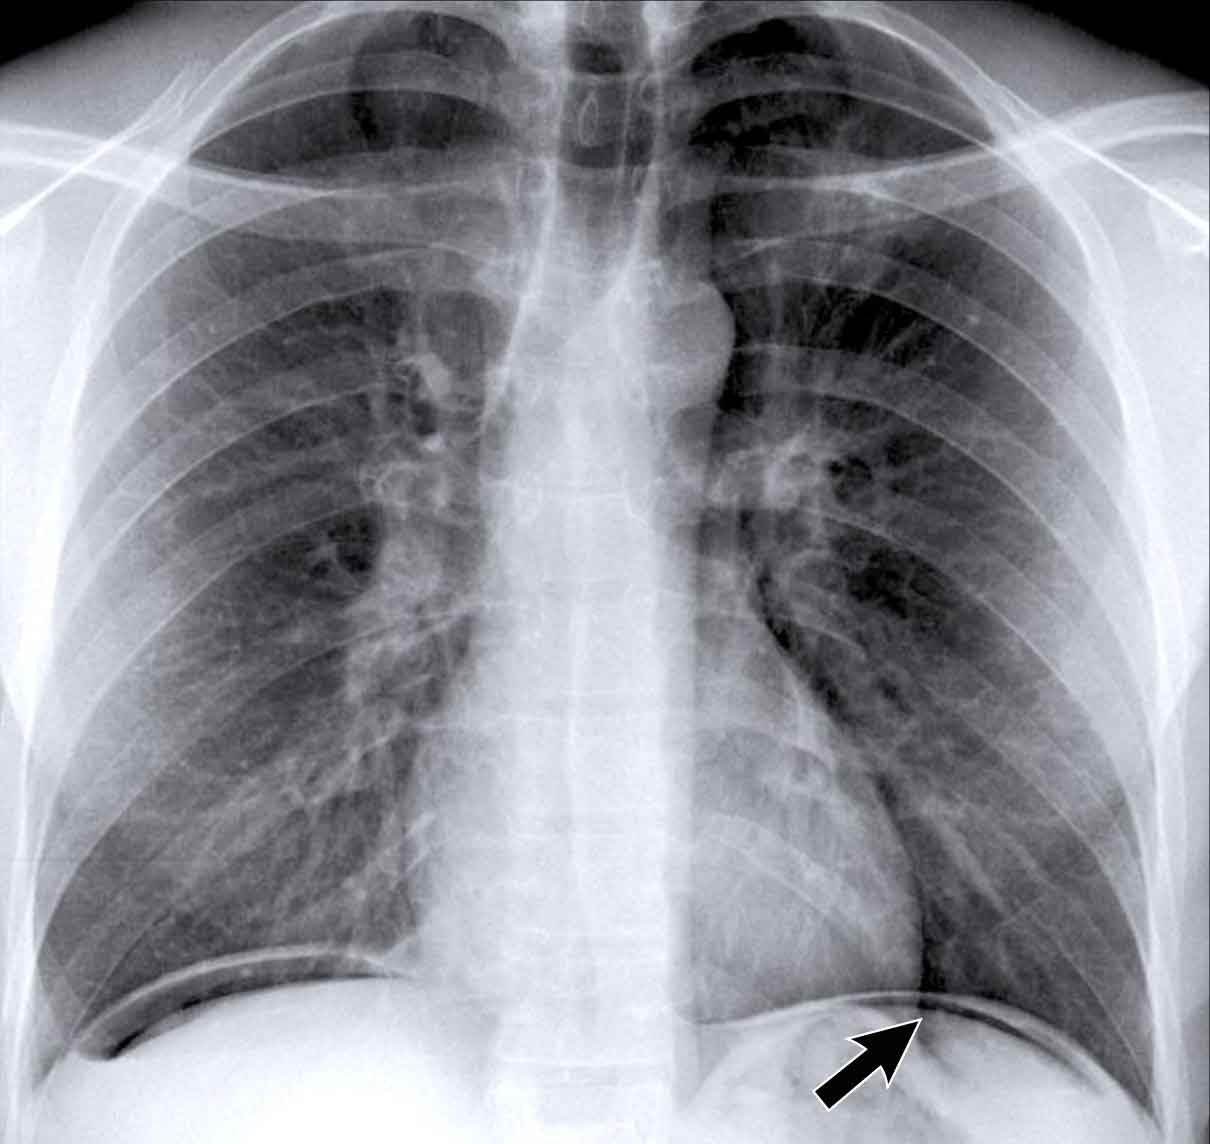

Silhouette sign

The silhouette sign refers to the loss of the normal border between structures of different radiographic densities, most commonly air-filled lung adjacent to soft tissue structures like the heart or diaphragm.

This sign is crucial for detecting subtle pathology and localizing lesions within the thorax.

Illustration of the Silhouette Sign

- No Silhouette Sign (Blue Arrow)- The left ventricle, located anteriorly, is normally bordered by air-filled lingula of the left upper lobe.

- If a consolidation occurs in the left lower lobe (posterior), the interface between the lingula and the heart remains intact, and the left heart border is preserved.

- Positive Silhouette Sign (Yellow Arrow)- When consolidation is present in the lingula, which directly abuts the left heart border, the silhouette of the left ventricle becomes obscured.

- This indicates the pathology is located anteriorly in the chest.

Silhouette Sign – Examples

Case 1: PA View

- The left heart border is obscured on the PA radiograph.

- Without even reviewing the lateral view, this finding localizes the pathology to the anterior segment of the left lung, likely the lingula.

- Diagnosis: Lobar pneumonia due to Streptococcus pneumoniae.

Case 2: PA View

- A consolidation is visible in the left lower lobe (yellow arrow).

- The left heart border remains well-defined with a normal silhouette (blue arrow), indicating the lesion is posterior, not involving the lingula.